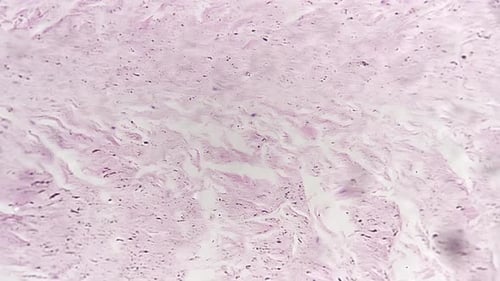

Dense Connective Tissue in Longitudinal Section Under Microscope 100x Against Bright Field

This close up shot features a microscopic view of tissue. The view pans up. This footage could be used in a medical project, focusing on health and science. This microscopic view is a good addition to any medical or science related visual project.